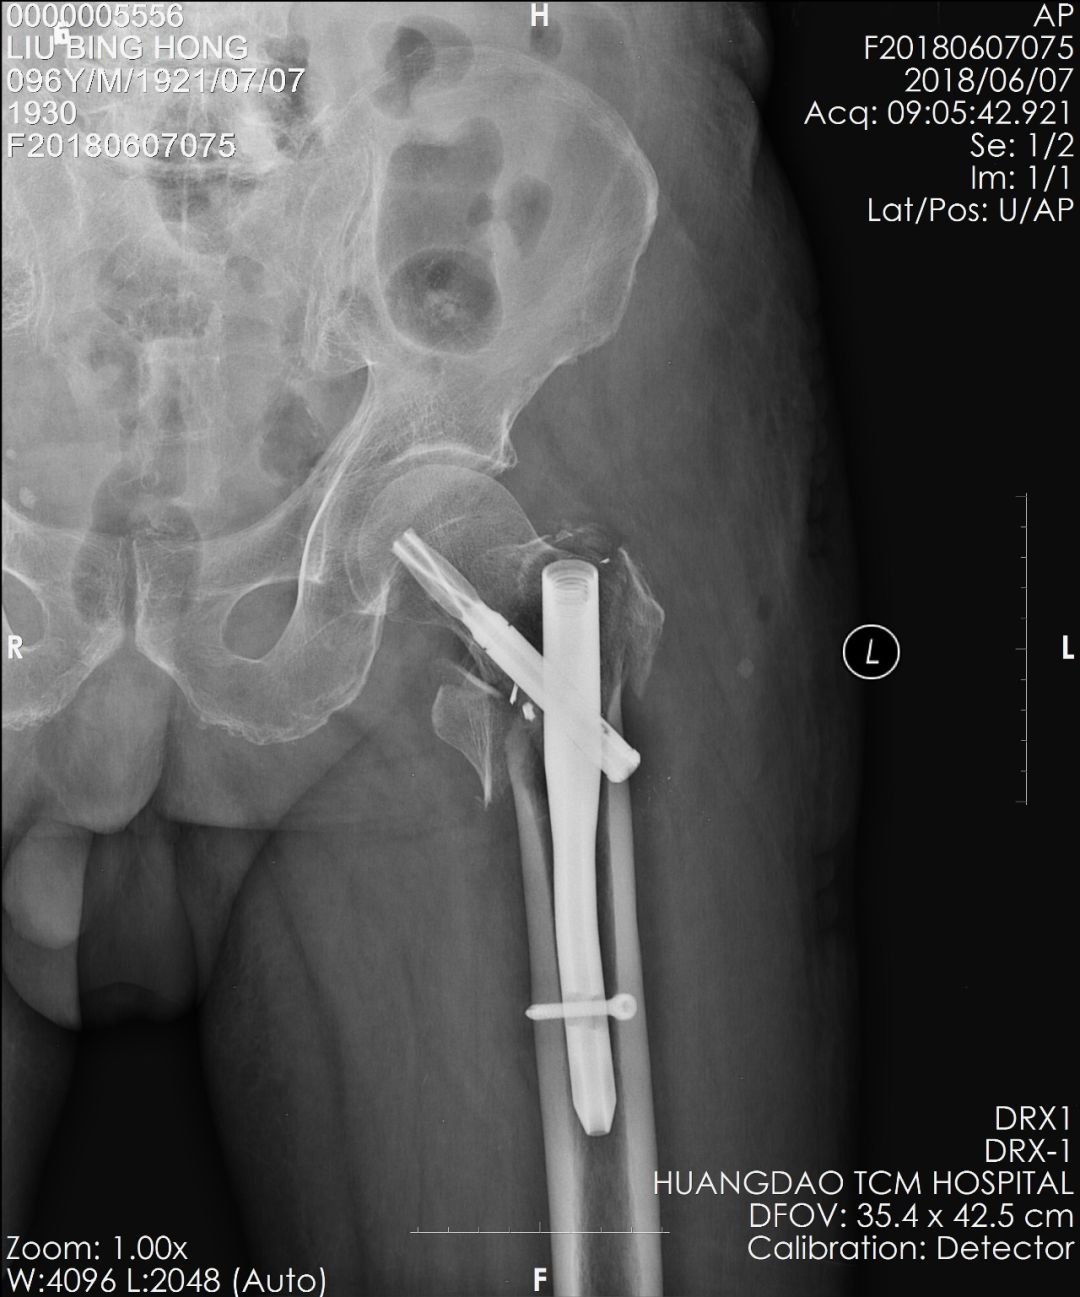

术后复查拍片

术后,刘大叔恢复良好,疼痛减轻,患肢活动良好,可扶拐下地行走。